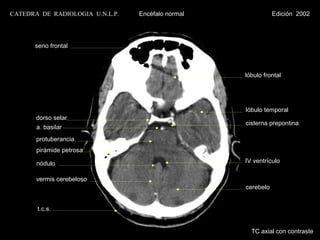

CATEDRA DE RADIOLOGIA U.N.L.P.   Encéfalo normal              Edición 2002

seno frontal

lóbulo frontal

lóbulo temporal

dorso selar

cisterna prepontina

a. basilar

protuberancia

pirámide petrosa

nódulo                                      IV ventrículo

vermis cerebeloso

cerebelo

t.c.s.

TC axial con contraste